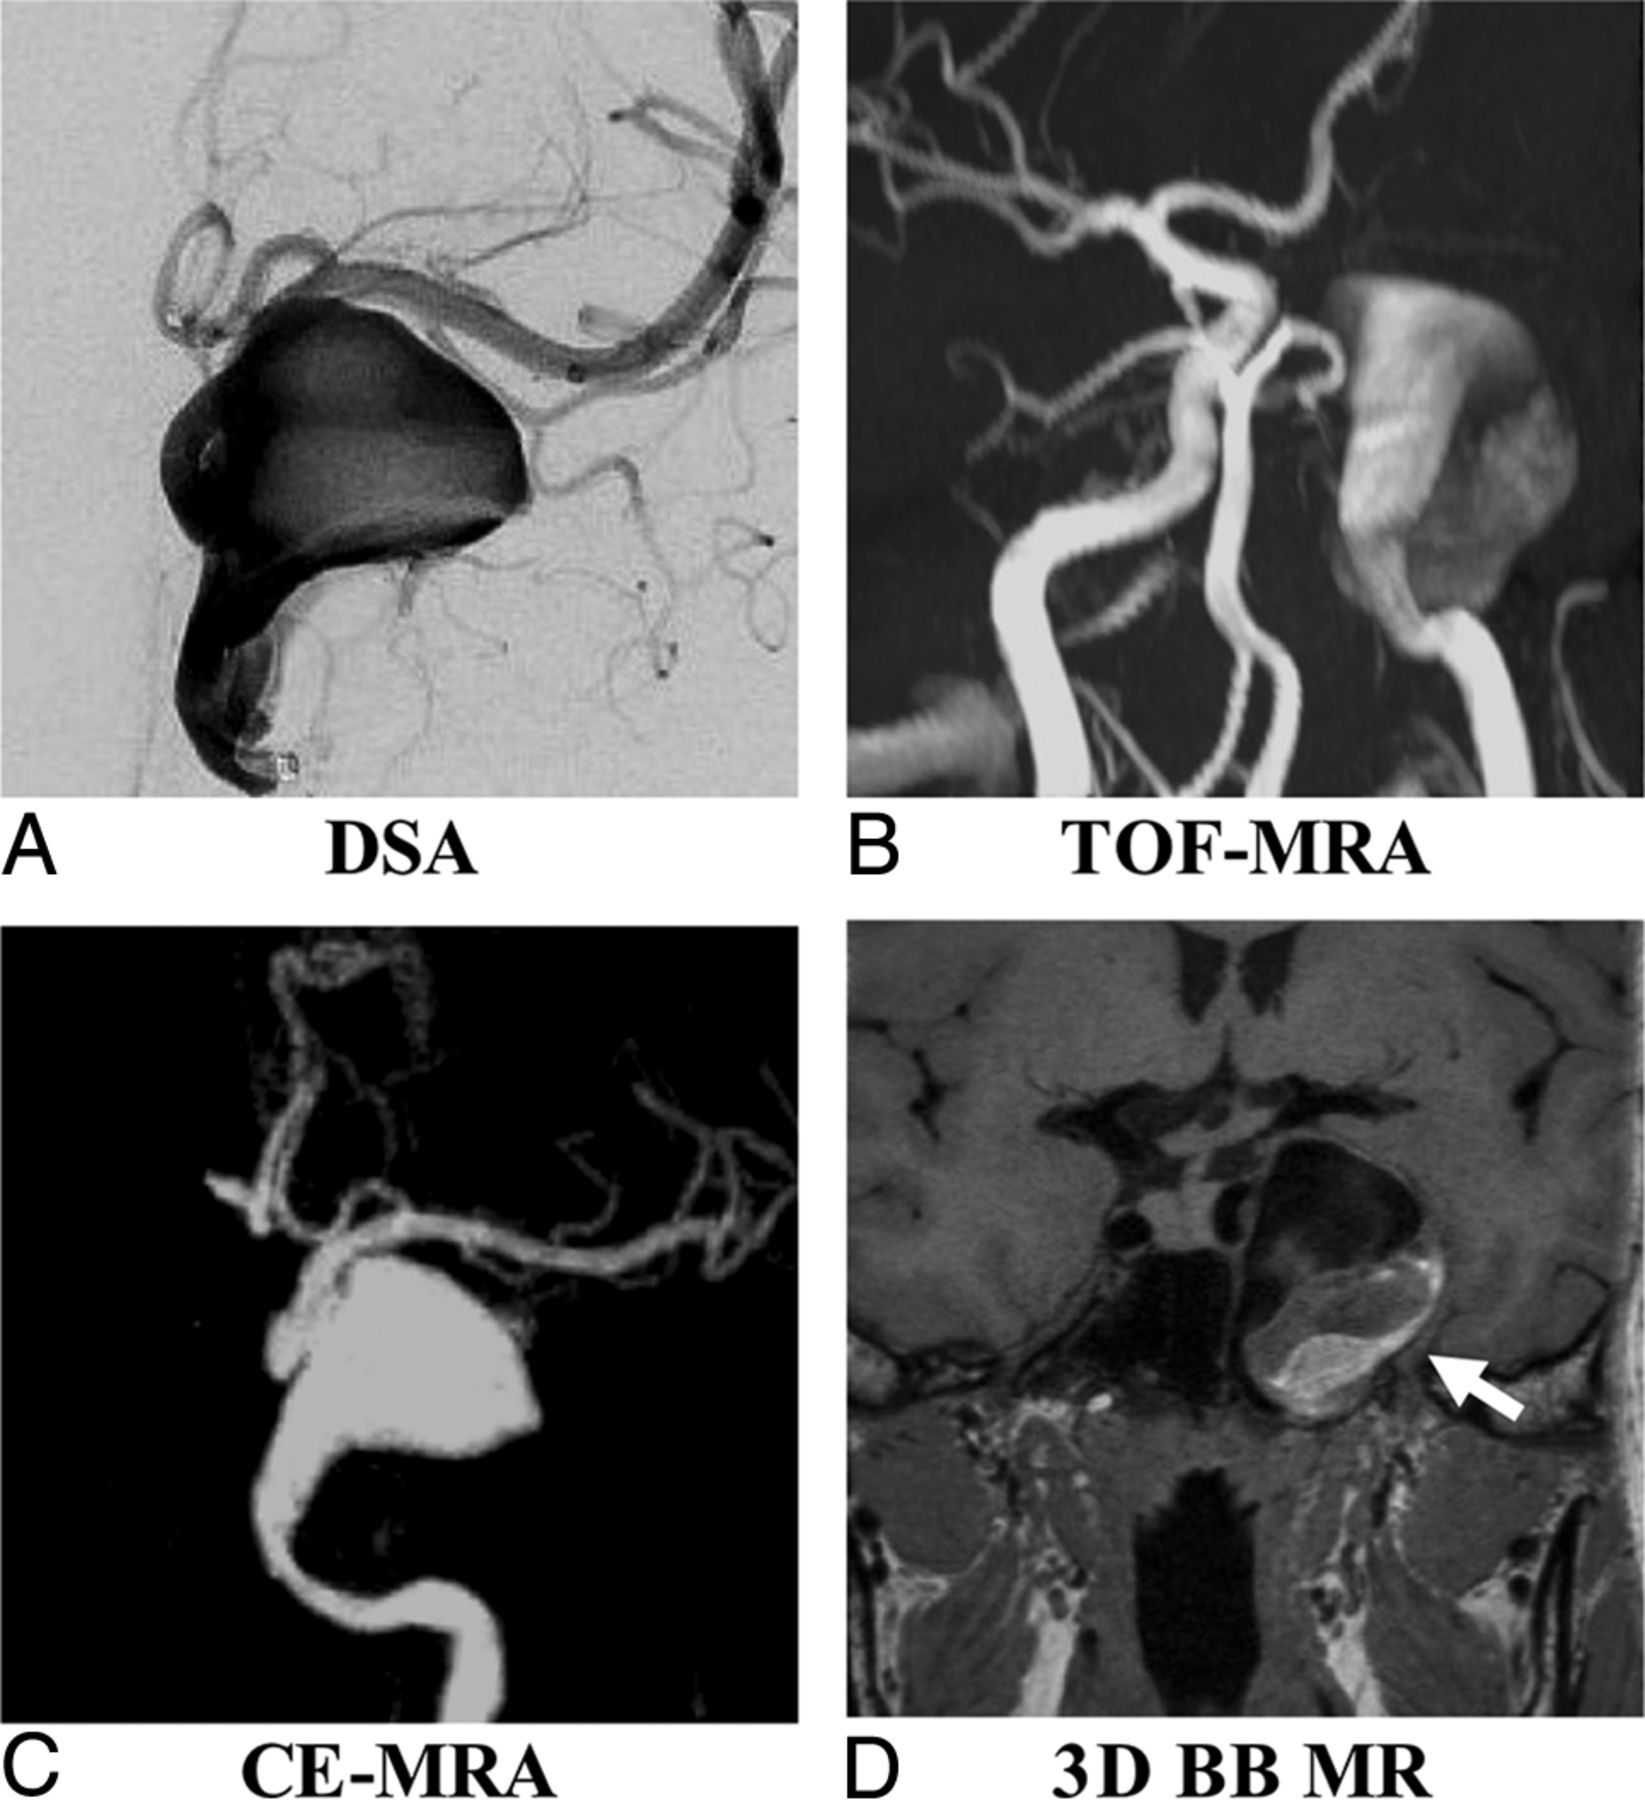

A 61-year-old woman with a right posterior communicating artery aneurysm on DSA (A), TOF-MRA (B), CE-MRA (C), and 3D-BB MR imaging (D). Aneurysm height (red line), width (yellow line), and neck (white line) measurements are demonstrated in A.

Sample patient images are shown in Figs 3 and 4. Figure 3 shows that TOF is limited as a means of displaying the aneurysm geometry due to severe flow artifacts, while DSA, CE-MRA, and SPACE characterize the geometry nicely. Figure 4 shows an aneurysm with intraluminal thrombus. 3D-BB MR imaging can clearly show the entire aneurysm structure including both the lumen and the thrombus.

A 53-year-old man with multiple basilar artery aneurysms on DSA (A). The aneurysm shows isointensity on TOF-MRA (B) because of the slow flow (arrow). The aneurysm sac and neck were integrally visualized on CE-MRA (C) and 3D-BB MR imaging (D).